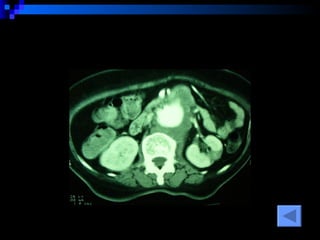

CT SCAN AAA juxtrareal -> bifurcation  Size 10*8*4 cm Inflamatory tissue  around AAA Intact renal artery Aortic dissection at juxtra renal -> bifurcation Bowel wall thickening at 3 rd -4 th  part of duodenum

CT SCAN AAAjuxtrareal -> bifurcation Size 10*8*4 cm Inflamatory tissue around AAA Intact renal artery Aortic dissection at juxtra renal -> bifurcation Bowel wall thickening at 3 rd -4 th part of duodenum